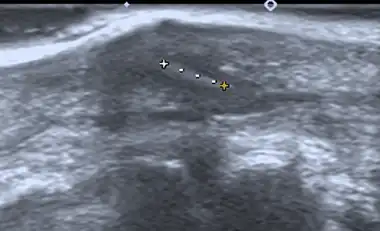

Ultrasonography of a subcutaneous splinter (in a finger) 4 x 1mm with oblique stroke.

If manual detection and localization fail, the main methods for medical imaging of splinters are:

• Medical ultrasonography – used to locate glass, metal, pencil graphite, some plastics, stone, and some types of wood.[6]

Small wooden splinters (1–4 mm) distant from bones are most easily detected by ultrasonography, while CT scan and magnetic resonance imaging have higher sensitivity for those near bones.[7]